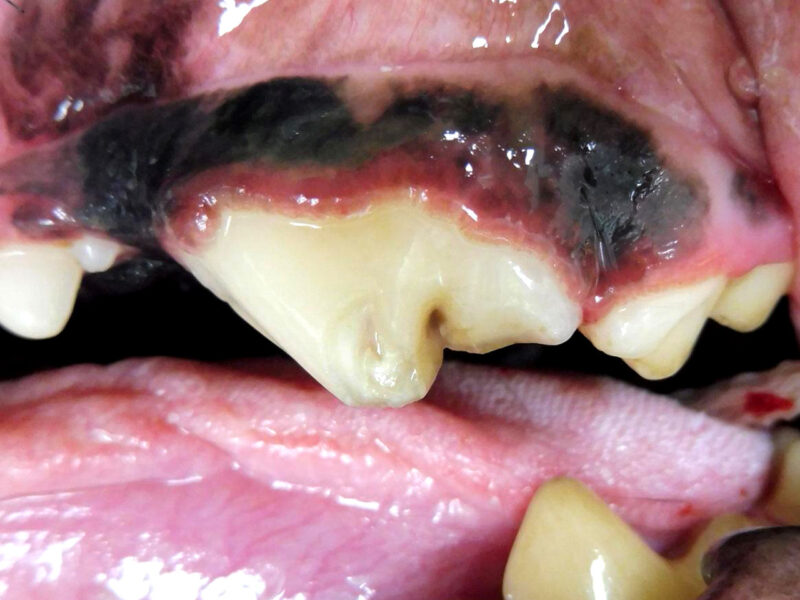

Bei Mia gibt es außer der bekannten Zahnfraktur des linken Oberkieferreißzahns (Prämolarer 4) keine Auffälligkeiten. Bei der Sondierung und Betrachtung der Bruchkante mit der Lupenbrille zeigt sich, dass noch eine ganz feine Schicht Zahnsubstanz (Dentin) Mias Wurzelkanal bedeckt. Das Dentin bietet zwar noch einen gewissen Schutz, im Gegensatz zum Zahnschmelz (der beim gesunden Zahn die äußerste Schicht der Zahnkrone bildet) hat es jedoch feine Kanälchen durch die Bakterien eindringen könnten. Im Röntgenbild zeigt sich bisher kein Hinweis für eine bestehende Infektion, und zusammen mit der Besitzerin wird entschieden, dass Mia den Zahn erstmal behalten darf, aber in sechs Monaten erneut zur Zahnröntgenkontrolle kommen muss. Da die feine Dentinschicht über dem Wurzelkanal weder vor Infektionen noch vor Umwelteinflüssen schützt, wird die Bruchkante mit dem Bohrer geglättet und der Zahn mit Kunststoff versiegelt.